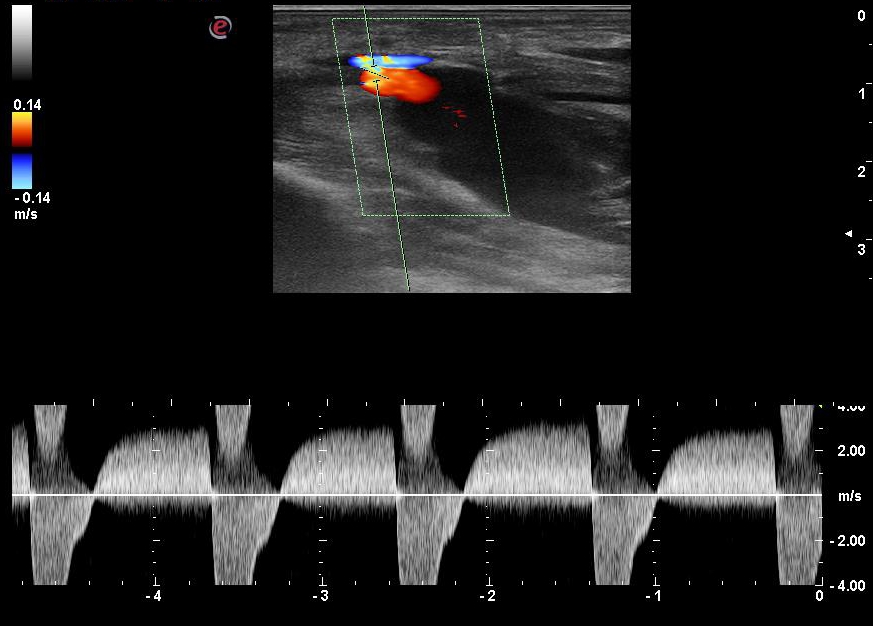

According to duplex scanning of the arteries of the upper limbs: the radial and ulnar arteries are patent, with the main type blood stream through them. The presence of a pseudoaneurysm along the posterior wall of the RA with low-resistance blood flow is noted (Figures 1, 2). The dimensions of the pseudoaneurysm of the RA are 16.4 × 13.5 mm in cross section.

Fig. 1. Duplex scan, spectral Doppler mode, longitudinal section. The blood flow in the neck of the pseudoaneurysm is shown.